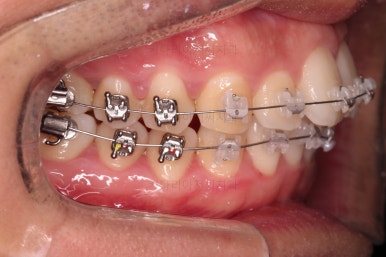

초진 시 입안의 모습입니다.

부정교합이 있고요.

옆쪽에서 보면 치아와 치아가 1:1로 부딪히는데(화살표 표시) 좋지 못한 교합입니다.

윗니와 아랫니가 앞뒤로 지그재그 서로서로 껴있어야 좋은 교합인데 전반적으로 윗니가 앞으로 밀려있는 양상의 교합이에요.

장기적으로 치아, 잇몸 건강에 좋지 못하답니다.

또한 눈에 띄는 모습은 앞니가 튀어나오고, 사이사이 틈새가 보인다는 점이에요.